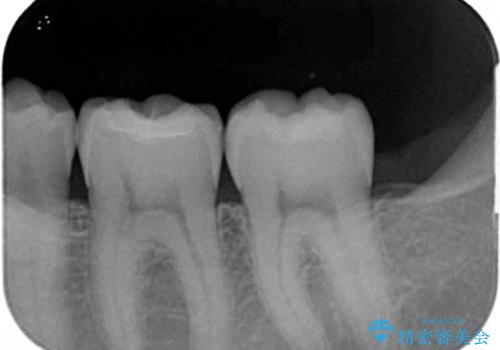

老朽化した銀歯の下には虫歯が大きくなっていることもあるので長期間経過した修復物はX線撮影を行うなどのチェックが重要です。